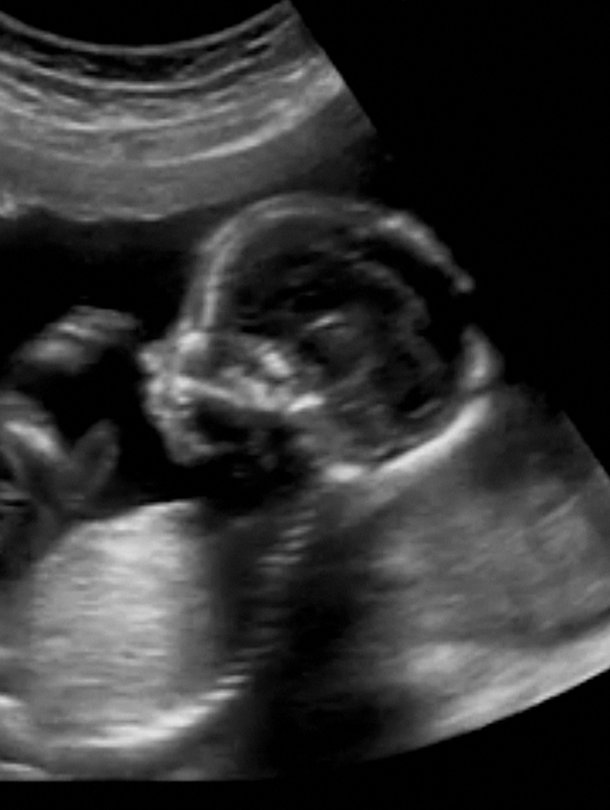

Ultraäänitutkimuksessa vauvasta otetaan ensimmäiset mitat. Muun muassa niiden perusteella arvioidaan, onko sikiö terve.

Mitä sikiöseulonta tarkoittaa? Terveydenhoitaja kertoo, mitä ultrassa tapahtuu